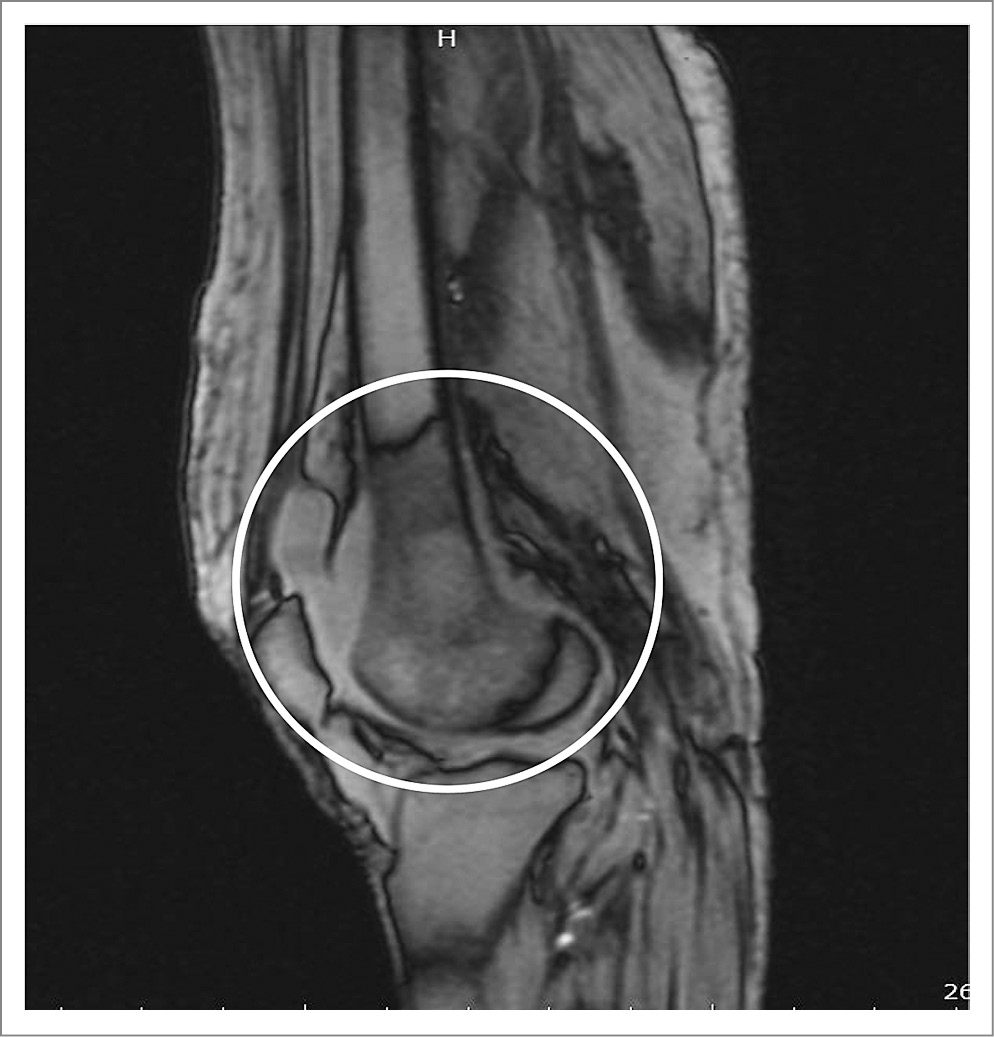

При попытке проведения магнитно-резонансной томографии (МРТ) правого коленного сустава (из-за выраженного тремора правой ноги исследование прекращено досрочно) удалось получить лишь несколько изображений, на которых патологические изменения напоминали признаки асептического некроза мыщелка правой бедренной кости с демаркационными линиями (рис. 1).

Рис. 1. МРТ правого коленного сустава. Признаки асептического некроза мыщелка правой бедренной кости с демаркационными линиями.